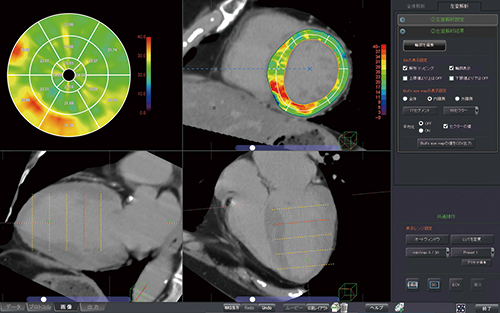

CT心筋ECV解析

心臓CTから細胞外容積分画(ECV)を算出してマッピングする。動きのある心臓の心筋を自動抽出し,複数の画像から数値を計算し画像に反映させるまで多くの計算能力を使って実現している。